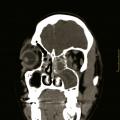

Rhinosinusite chronique de l’adulte et mucoviscidose

La mucoviscidose est la maladie autosomique récessive la plus fréquente dans la population caucasienne. La majorité des cas sont diagnostiqués dans l’enfance, avec une incidence de 1 cas pour 3 200 naissances. Toutefois, les cas découverts à l’âge adulte sont de plus en plus souvent observés. Ainsi, le nombre de patients…